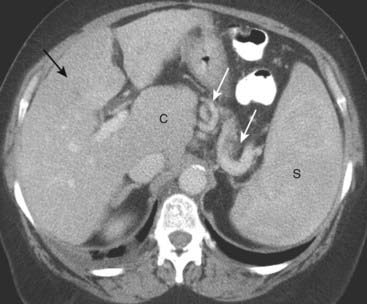

Fatty Infiltration

imageFatty infiltration (also known as hepatic steatosis) of the liver is a very common abnormality in which there is fat accumulation in the hepatocytes in such diseases as alcoholism, obesity, diabetes, hepatitis, or cirrhosis. Most patients with a fatty liver are asymptomatic. The fatty infiltration may be diffuse or focal, and focal lesions may be solitary or multiple.

image When diffuse, the liver is usually slightly enlarged. The blood vessels stand out prominently but are usually neither obstructed nor displaced.

image Normally, on noncontrast CT scans, the liver is always denser than or equal to the density of the spleen. With fatty infiltration of the liver, the spleen is denser than the liver without intravenous contrast (Fig. 18-27).

image

Figure 18-27 Diffuse fatty liver (hepatic steatosis).

Normally, on noncontrast CT scans, the liver is always denser than or equal to the density of the spleen. In this patient with diffuse fatty infiltration of the liver, the spleen (S) is denser than the liver (solid white arrow). Notice how the vessels stand out in the fatty liver (dotted white arrow). (K = kidneys.)